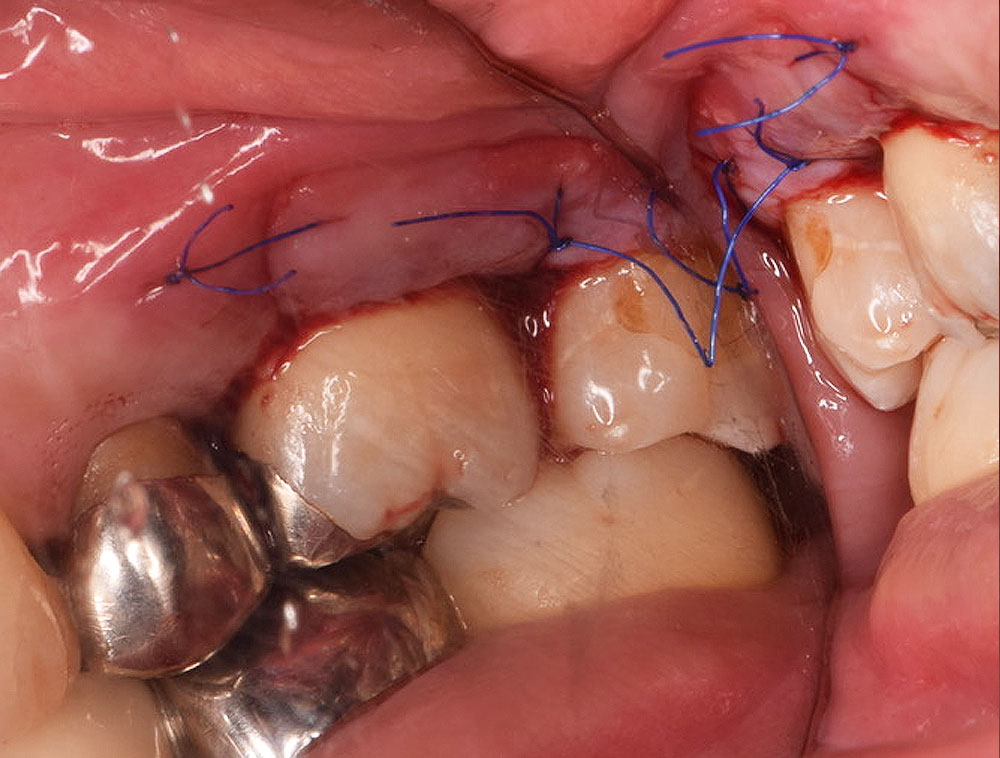

治療ステップ3歯周再生療法

EMD による再生治療は外科的なアプローチをともない行います。まず歯肉を切開・剥離して歯根と歯槽骨を見えやすい状態にします。この状態でそれまで(歯肉縁下の)歯茎に隠れていた歯根先端部についた歯石、歯周病に感染したセメント質を清掃・除去します。